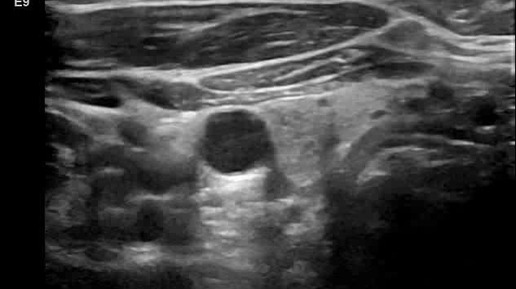

Видео к статье "Стратификация узлов щитовидной железы. TI-RADS-2"Адрес: https://dzen.ru/a/ZuUZLzUfMV_UqGyz